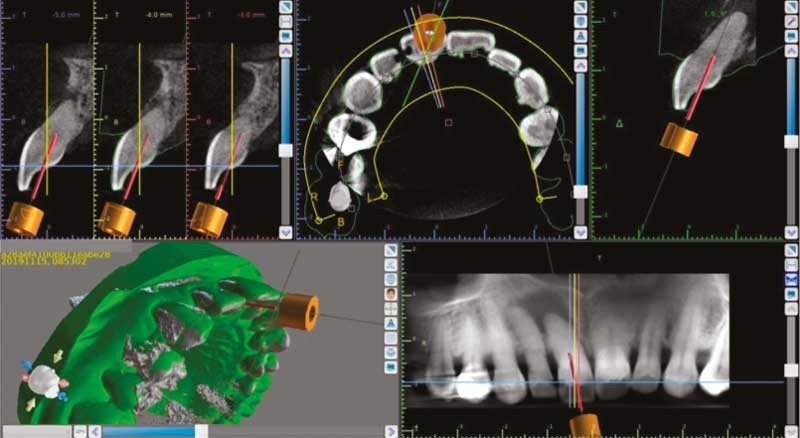

La Société Européenne d’Endodontie (European Society of Endodontology – ESE) est à l’origine de recommandations quant aux indications de l’imagerie tridimensionnelle dite Tomographie Volumique à Faisceau Conique ou CBCT (Cone Beam Computed Tomography) [1]. Dans de nombreuses situations endodontiques, l’utilisation du CBCT se révèle nécessaire, par exemple pour aider au diagnostic, mieux caractériser les structures anatomiques et l’anatomie canalaire en préopératoire, évaluer une lésion inflammatoire péri-radiculaire d’origine endodontique (LIPOE) ou encore assurer un suivi de traitement (fig. 1). Cet examen de seconde intention ne doit cependant pas être généralisé et son indication doit respecter le principe ALADAIP (As Low As Diagnostically Achievable Being Indication-oriented and Patient-specific) [2].